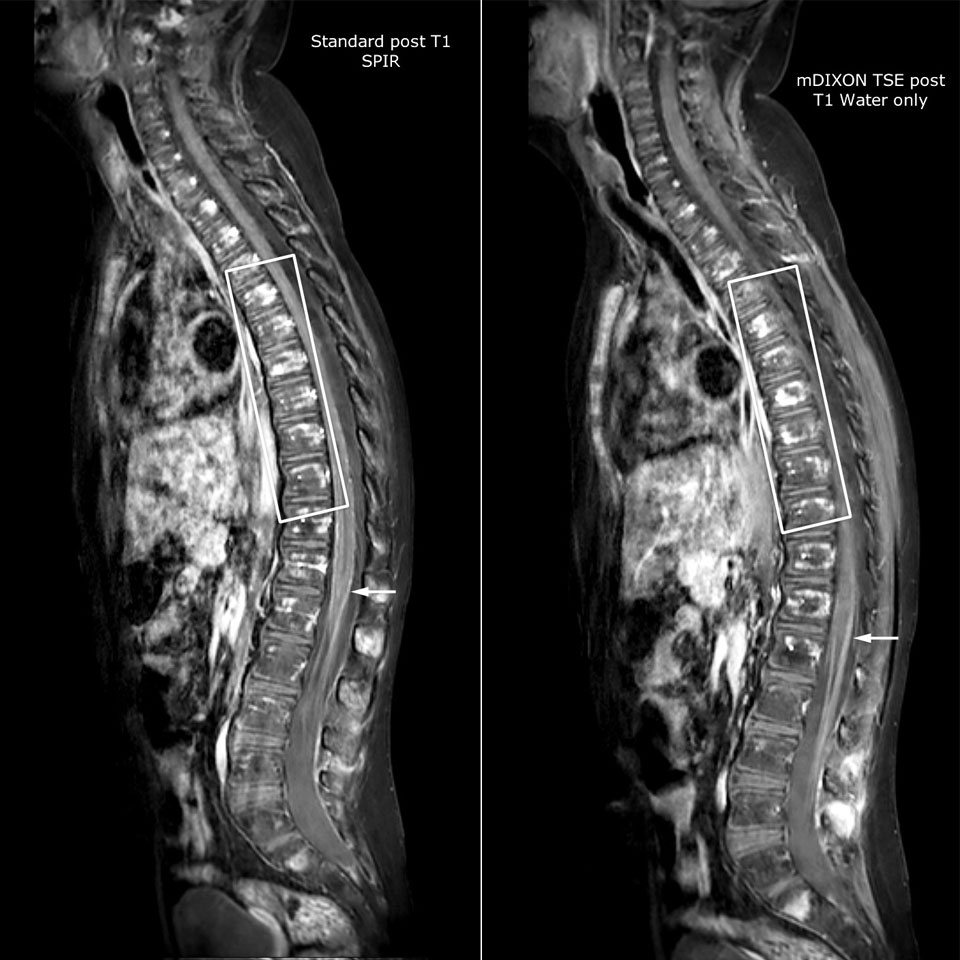

Philips mDIXON TSE is a two-point DIXON technique that separates water and fat signals, for time-efficient fat-free imaging, even in challenging neuro anatomy. “mDIXON TSE has been one of the most significant improvements in imaging sequences that we have utilized to date at PCH,” says Dr. Miller. “Its multi-parametric acquisition allows us to obtain fat suppressed images and equivalent non-fat suppressed T2 images all in the same sequence. In addition, prior methods of fat suppression could be artifactually corrupted by poor patient anatomy or poor operator application, but with mDIXON we now have a robust and reliable method of fat suppression.” Fat saturation is historically challenging at the ends of fields of view, especially in total spine imaging and in difficult patient anatomy such as the lower regions of the neck. “Due to the unique fat suppression capabilities of mDIXON, however, these challenges no long apply,” says Dr. Miller. “We routinely obtain homogeneous fat suppression under virtually all conditions. It has also led to some efficiencies by not having to repeat sequences because of that technical failure.”

“mDIXON TSE has increased our diagnostic confidence in ruling in or ruling out abnormalities in which fat suppression is critical to diagnosis, such as metastatic disease or osseous abnormalities.”

“mDIXON TSE is most useful in patients with lesions or abnormalities in the soft tissues such as the face and neck, and for patients with contrast enhancing abnormalities that are mostly visible with fat suppression,” says Dr. Miller. “All our spine imaging now routinely contains mDIXON water-only T2 images, and this allows us to identify pathology that may be obscured by non-fat suppressed imaging such as injuries of the bone. And it’s not necessary to obtain additional standard TSE T2 images because the in-phase mDIXON images are equivalent to standard TSE T2 images.”

Goetti R, O'Gorman R, Khan N, Kellenberger CJ, Scheer I. Arterial spin labelling MRI for assessment of cerebral perfusion in children with moyamoya disease: comparison with dynamic susceptibility contrast MRI. Neuroradiology. 2013 May; 55(5):639-47, Epub 2013 Feb https://www.ncbi.nlm.nih.gov/pubmed/23404242 Miller JH, Pokorney A, Naidu P, Eggers H, Shar M, Perkins T. Improved Fat Suppression and Field Homogeneity of mDixon TSE Total Spine Imaging compared to SPIR Fat Saturation for Post-Contrast T1-weighted Imaging. Proceedings of the Joint Annual Meeting of the ISMRM-ESMRB. Milan, Italy: International Society for Magnetic Resonance in Medicine, 2014.